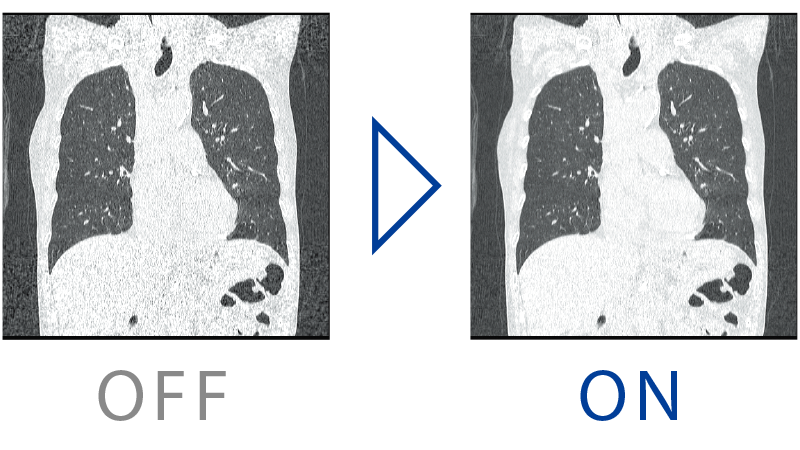

HiMAR (High Quality Metal Artifact Reduction) estimates and correctes artifacts based on metal data.